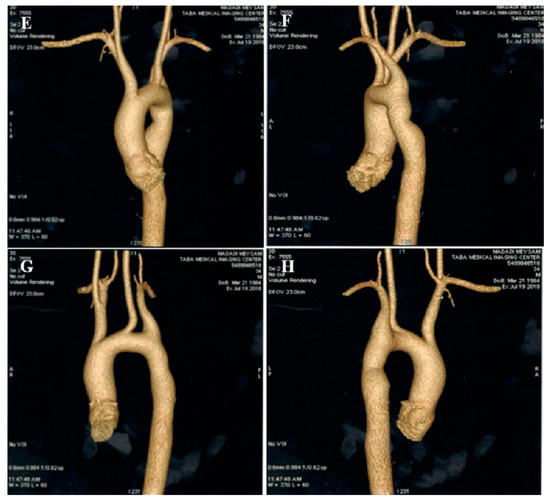

2.1. Case #1. NCLV and Coarctation of the Aorta

A 47-year-old gentleman who worked in the military service for 15 years was referred to our clinic with a complaint of easy fatigability and mild hypertension since 2 years ago. He was followed up with by another colleague who had the impression of mild LV systolic dysfunction and subaortic web. He received 5 mg daily amlodipine; but had mildly raised blood pressure (BP; 140/90 mmHg). When he was referred to our center, there was a discrepancy between the upper and lower extremities’ BP, and cardiac auscultation revealed a loud A2 closure sound. The review of the previously performed CXR showed posterior rib notching at three points. Computed tomography angiography of the aorta confirmed the presence of post-ductal narrowing in the descending aorta. TTE and TEE showed NCLV with mild LV systolic dysfunction (LVEF = 45%) and coarctation of the aorta with a 28 mmHg rest gradient across the coarctation site. CMR confirmed the diagnosis of NCLV (Figure 1). No other associated pathology was noted. A genetic study showed mutations in the MYH7 and MYBPC3 genes; the genetic and echocardiographic results of his siblings (one sister and two brothers) were normal. The patient was recommended to use carvedilol 6.25 mg (three times a day) and spironolactone 25 mg daily. At 1-year follow-up, the patient’s complaints had reduced and the BP was stable.

Figure 1.

The imaging results of case #1. (A); Left ventricular apical short-axis view illustrating hypertrabeculated apical portions in addition to deep intertrabecular recesses, (B); Color Doppler echocardiography, showing evidence of direct blood flow from the ventricular cavity into deep intertrabecular recesses (C); Speckle tracking echocardiographic findings, compatible with myocardial performance impairment plus relative apical sparing; GLS = −10.4%. (D); Prominent trabecular network in the apical lateral segments, (E–H); Thoracic CT angiography, showing narrowing of descending aorta, distal to left subclavian artery in different projections.